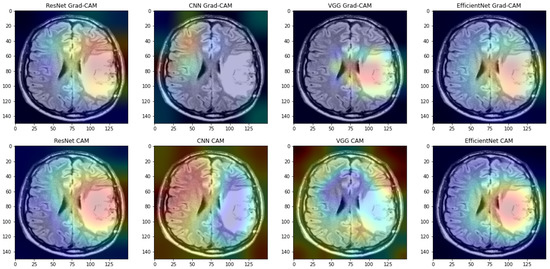

3.3. Results Obtained by the CAM and Grad-CAM Methods

- -

- denotes the percentage average value of the difference between the average Cartesian distance of CoM for the CAM and Grad-CAM methods,

- denotes the percentage average value of the difference between the average IoU value for the CAM and Grad-CAM methods.